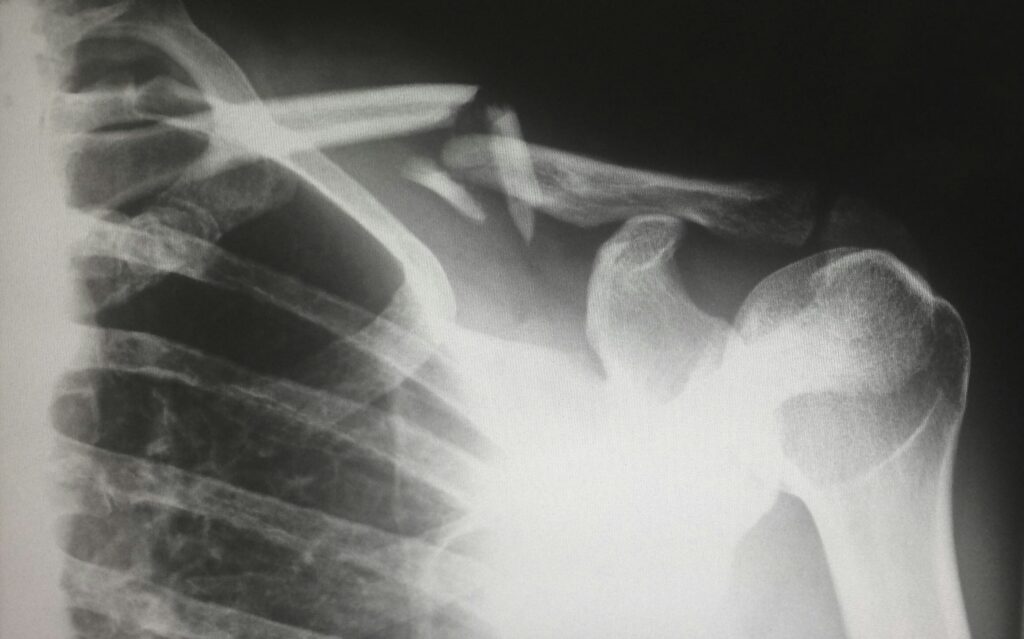

hip fracture

Credit: Unsplash/CC0 Public Domain